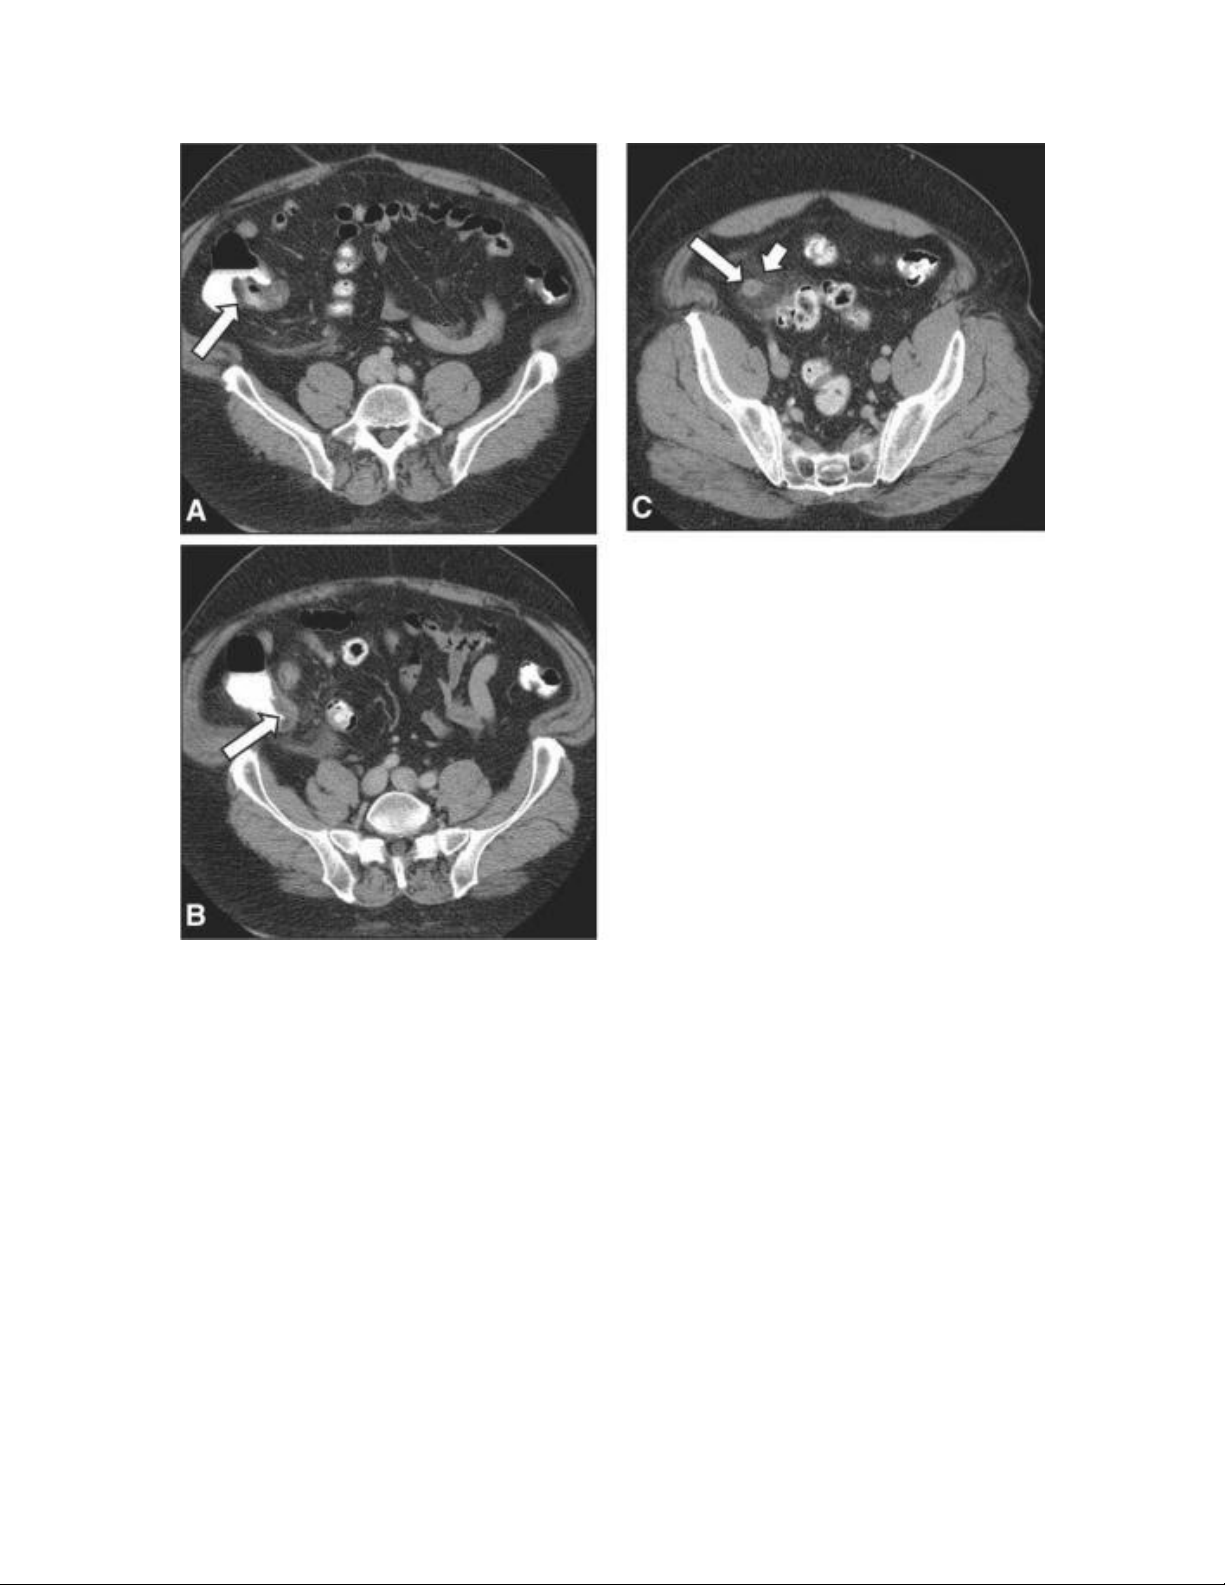

Hình 1. Viêm ruột thừa cấp. A và B: A nam 61 tuổi đau hố chậu

phải 1 ngày và buồn nôn. CT cản quang tĩnh mạch và đường uống

thấy van hồi manh tràng chứa mỡ (A, mũi tên) và lỗ ruột thừa ở

phía dưới một chút (B, mũi tên). C, ruột thừa (mũi tên dài) dày

thành và chướng đường kinh 14mm. Tăng đậm độ mỡ quanh ruột

thừa (mũi tên ngắn) chứng tỏ viêm quanh ruột thừa. Các dấu hiệu

CT phù hợp với viêm ruột thừa, được xác nhận lúc phẫu thuật và

bệnh học.